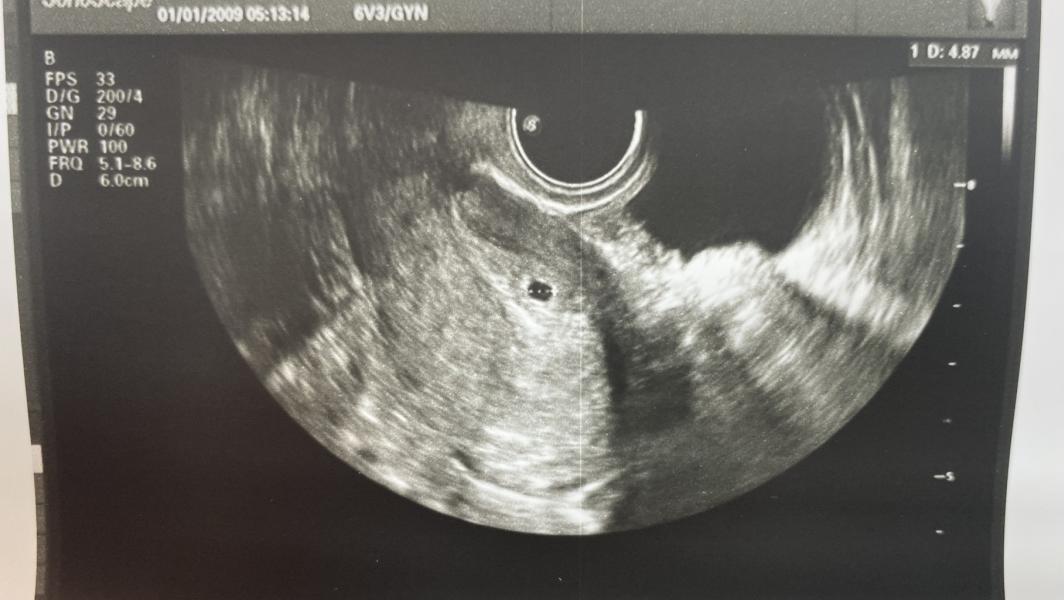

ХГЧ 957 и маточная беременность: первая радость

Мы увидели пя 🫶🏻 при хгч 957

Слава Богу маточная 🙏🏻🙏🏻🙏🏻